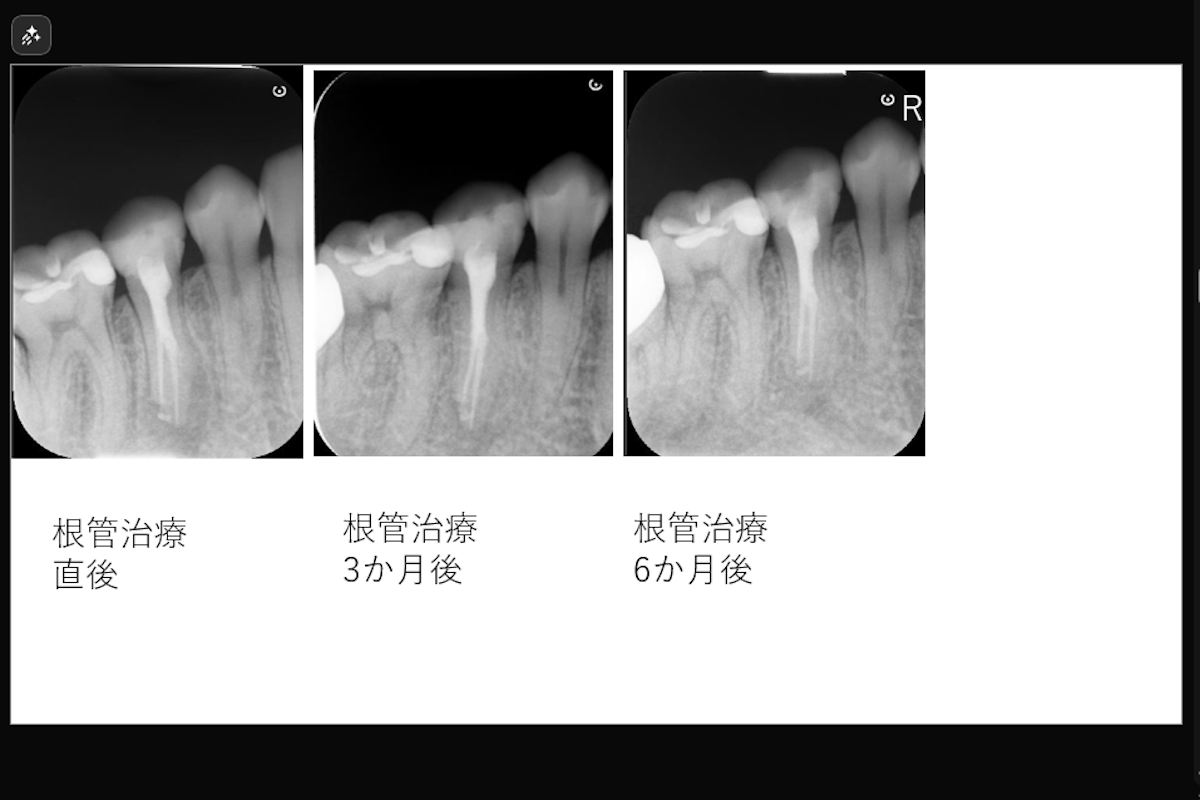

【根尖部外部吸収を伴う2根管性下顎第二小臼歯の症例】「近医で根管治療するも咬むと痛い。」

「近医で根管治療するも咬むと痛い。」ということで来院された患者様の症例です。

• 根尖部外部吸収を伴う2根管性下顎第二小臼歯の症例

• 治療内容: 下顎右側第二小臼歯 根管治療(レーザーを用いた根管洗浄、MTAを用いた根管充填)

• 治療のリスク: 残存歯質の厚みによって歯根破折のリスク、経過によっては外科的歯内療法